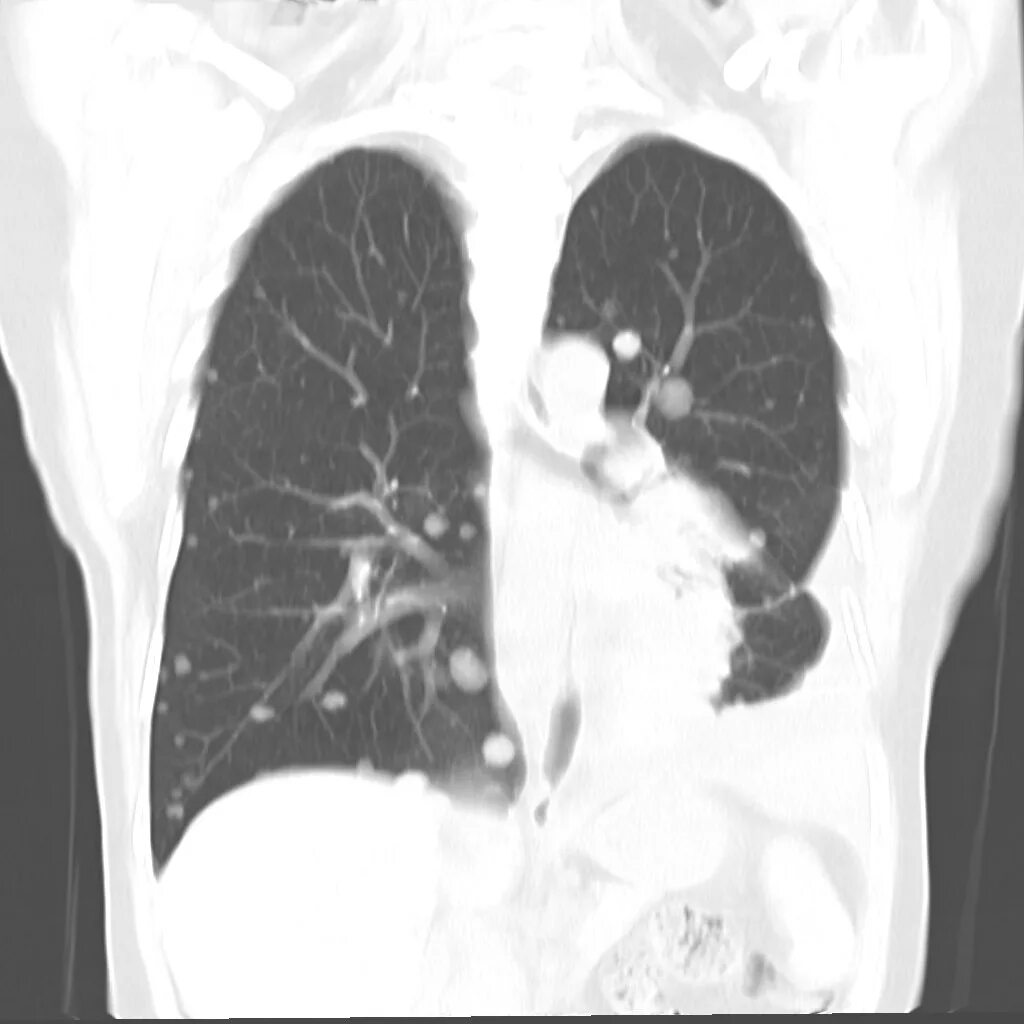

Метастазы в легких терапия